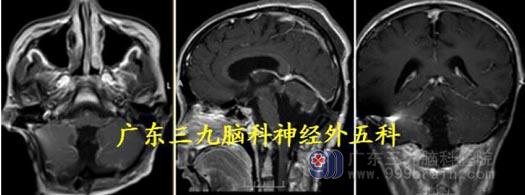

头颅MR:第四脑室-小脑蚓部示一囊实性占位性病变,范围约5.6×4.9×6.2cm,以囊性成分为主,增强扫描不均匀轻度-明显强化,实性部分向上凸入中脑导水管,脑干及小脑受压。考虑毛细胞星形细胞瘤可能性大。